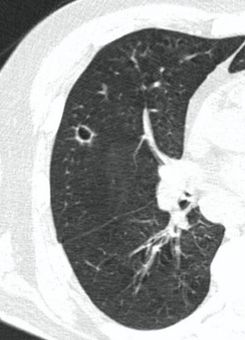

4.3. ЛУЧЕВАЯ ДИАГНОСТИКА COVID-19

Методы лучевой диагностики применяют для выявления COVID-19 пневмоний, их осложнений, дифференциальной диагностики с другими заболеваниями легких, а также для определения степени выраженности и динамики изменений, оценки эффективности проводимой терапии.

К методам лучевой диагностики патологии ОГК пациентов с предполагаемой/установленной COVID-19 пневмонией относят:

- Компьютерную томографию легких (КТ),

КТ имеет высокую чувствительность в выявлении изменений в легких, характерных для COVID-19. Применение КТ целесообразно для первичной оценки состояния ОГК у пациентов с тяжелыми прогрессирующими формами заболевания, а также для дифференциальной диагностики выявленных изменений и оценки динамики процесса. КТ позволяет выявить характерные изменения в легких у пациентов с COVID-19 еще до появления положительных лабораторных тестов на инфекцию с помощью МАНК. В то же время, КТ выявляет изменения легких у значительного числа пациентов с бессимптомной и легкой формами заболевания, которым не требуется госпитализация. Результаты КТ в этих случаях не влияют на тактику лечения и прогноз заболевания при наличии лабораторного подтверждения COVID-19. Поэтому массовое применение КТ для скрининга асимптомных и легких форм болезни не рекомендуется.

3. Применение лучевых методов у пациентов с симптомами ОРВИ легкой степени тяжести и стабильном состоянии пациента, возможно только по конкретным клиническим показаниям, в том числе при наличии факторов риска, при условии достаточных технических и организационных возможностей. Методом выбора в этом случае является КТ легких по стандартному протоколу без внутривенного контрастирования или РГ при ограниченной доступности КТ. Использование УЗИ в этих случаях нецелесообразно. Применение КТ исследования в сроки ранее 3 - 5 дней с момента появления симптомов заболевания является нецелесообразным.